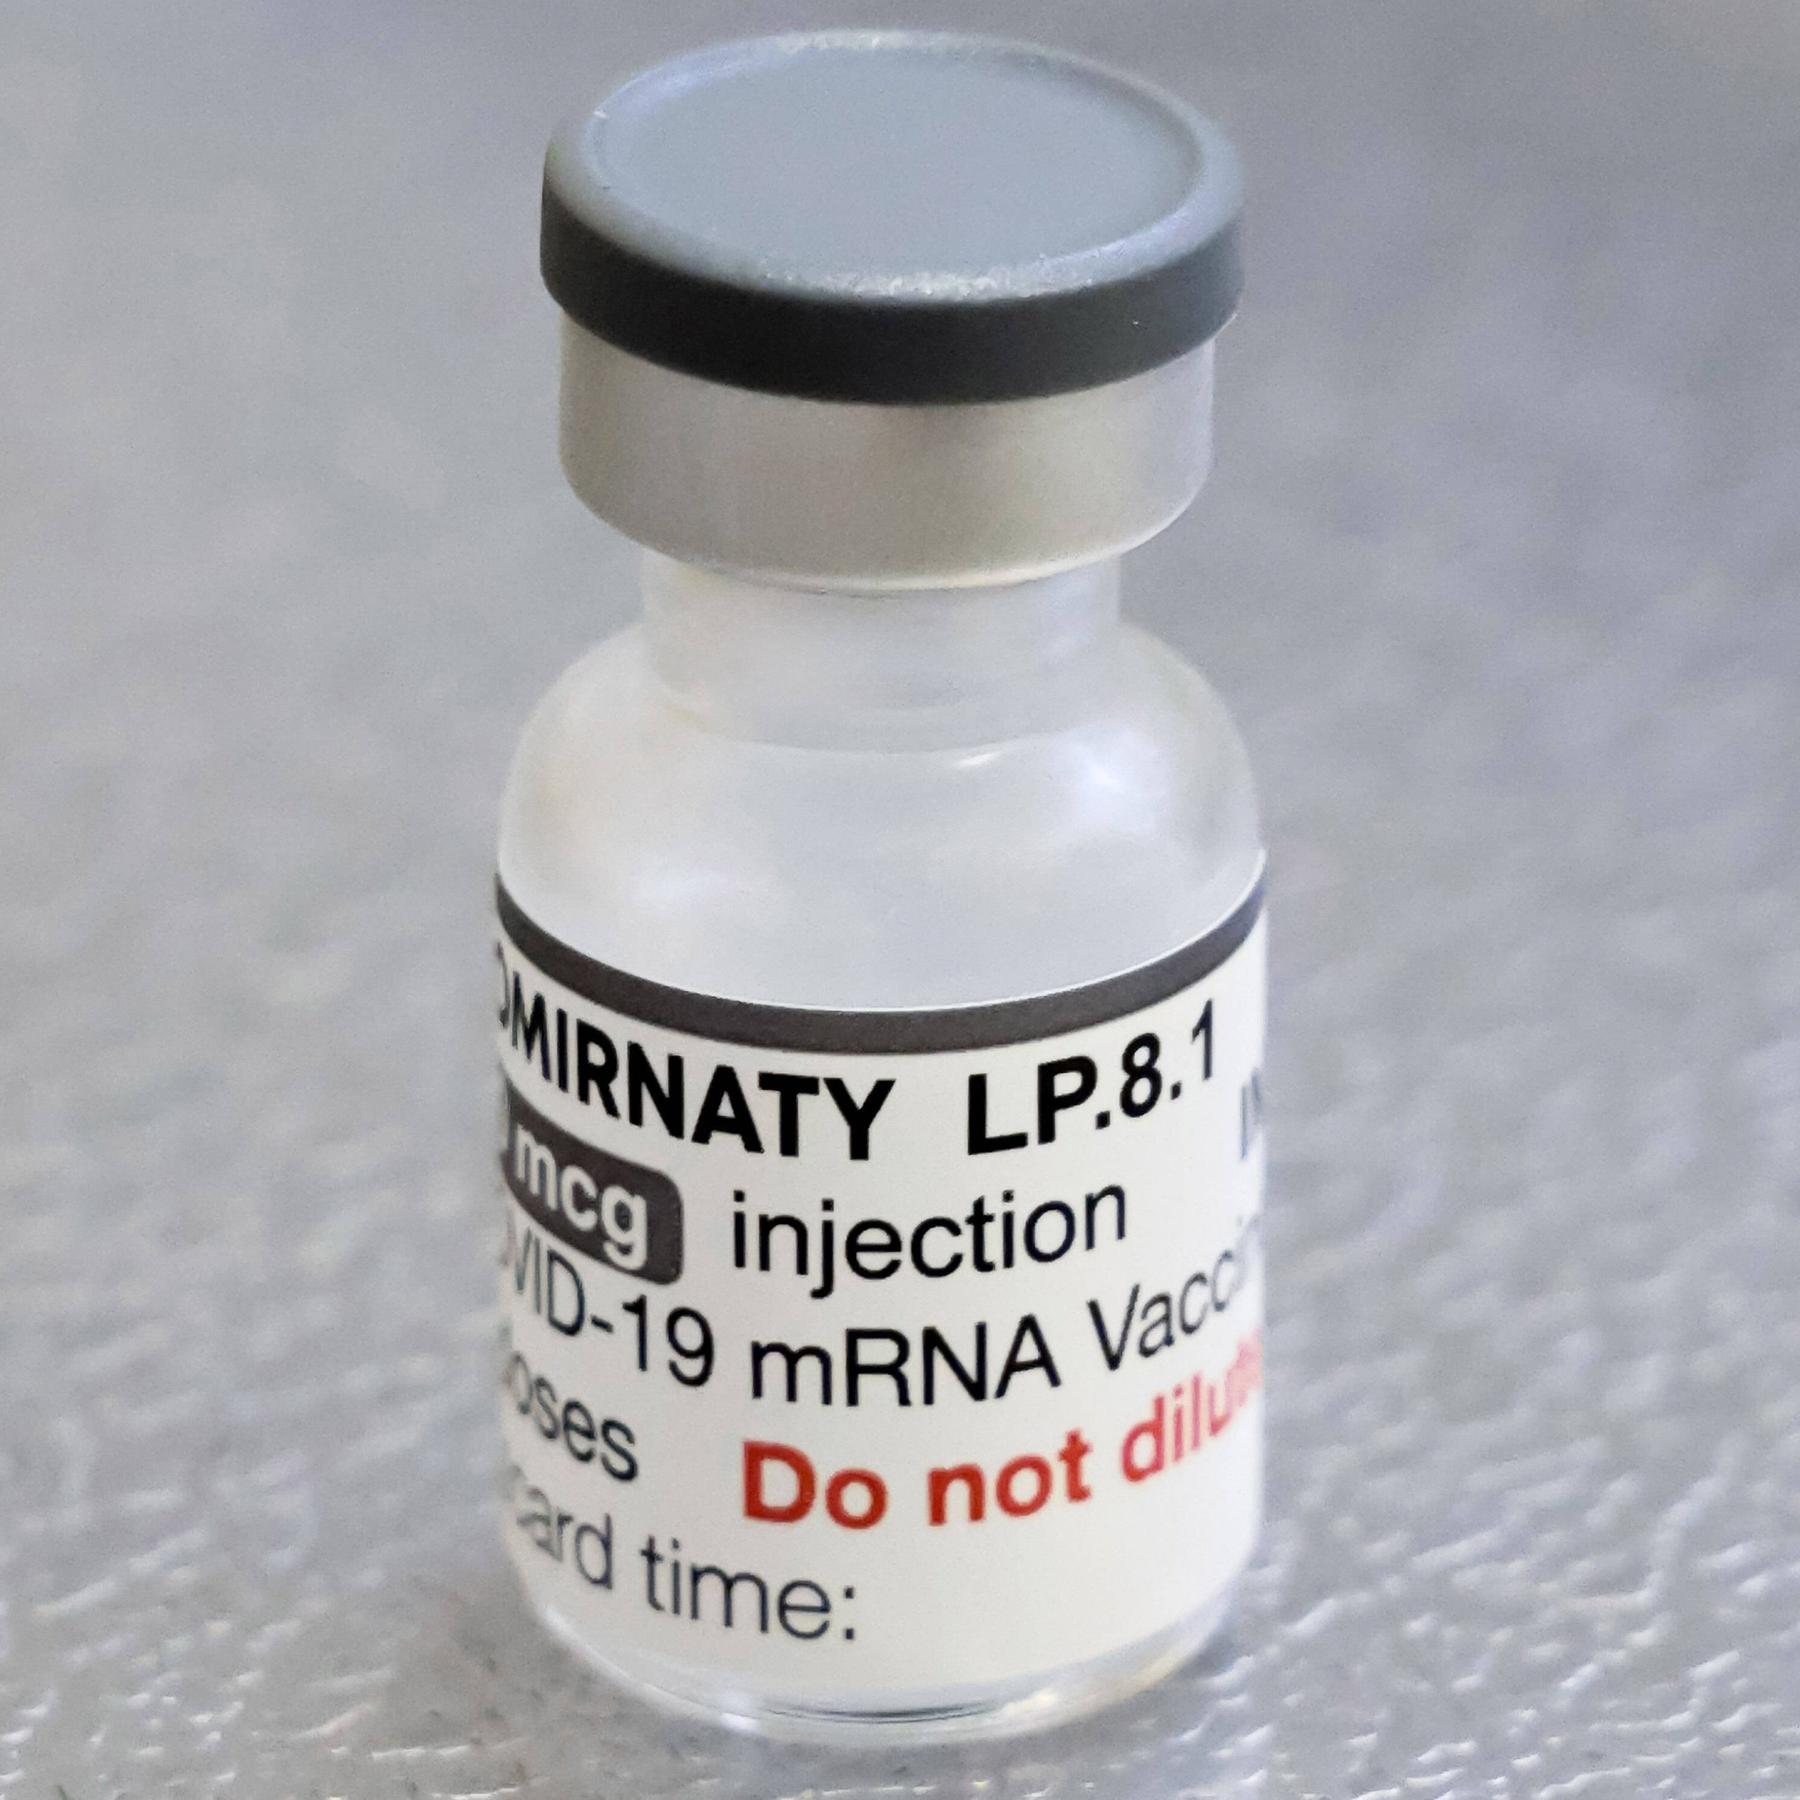

Die Corona-Impfung hilft Krebs-Patienten: Eine Studie zeigt, dass krebskranke Menschen deutlich länger lebten, wenn sie zusätzlich zu ihrer Immuntherapie gegen Krebs eine mRNA-Impfung gegen Covid-19 erhalten haben.

Die Corona-Impfung hilft Krebs-Patienten: Eine Studie zeigt, dass krebskranke Menschen deutlich länger lebten, wenn sie zusätzlich zu ihrer Immuntherapie gegen Krebs eine mRNA-Impfung gegen Covid-19 erhalten haben. Was dahinter steckt, erzählen wir in dieser Podcast-Folge.